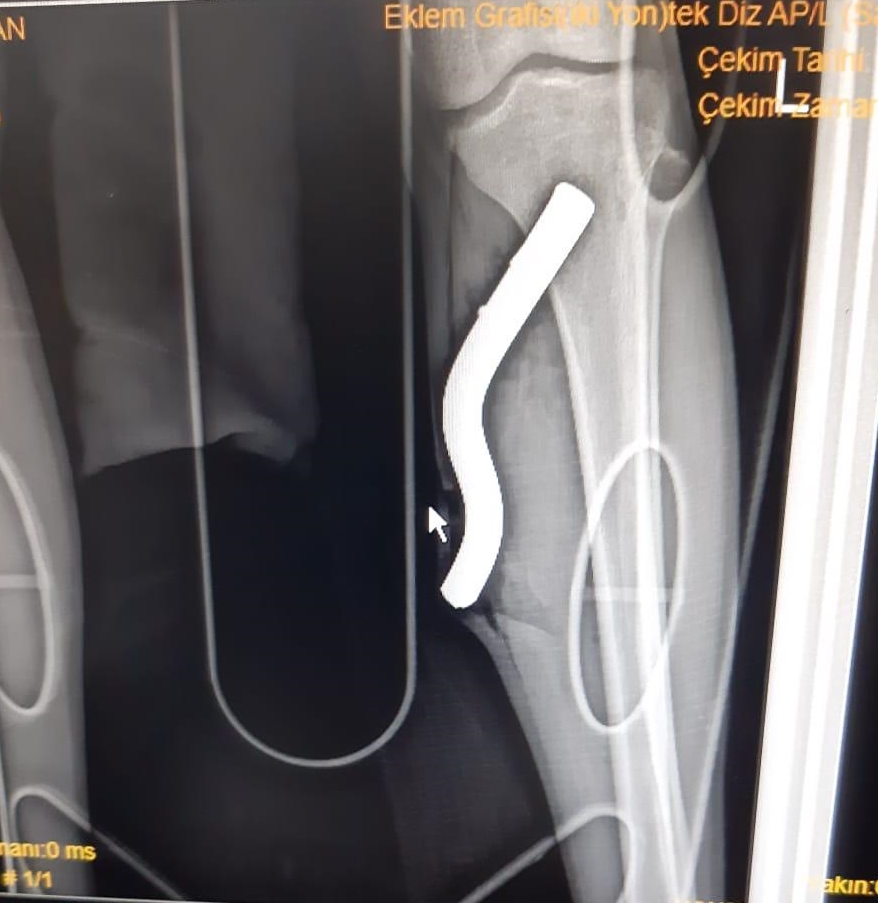

Ordu'da otomobil ile çarpışan motosikletin sürücüsünün bacağına saplanan pedal çubuğu operasyonla çıkarıldı.

Kullandığı motosikletin pedal çubuğu sol bacağına saplanan Çelik, kaldırıldığı Ordu Üniversitesi Eğitim ve Araştırma Hastanesinde tedavi altına alındı.

Ortopedi ve Travmatoloji Anabilim Dalı Başkanı Doç. Dr. Alper Çıraklı tarafından hastanenin acil bölümünde gerçekleştirilen operasyonda, Çelik'in bacağındaki pedal çubuğu çıkarıldı.